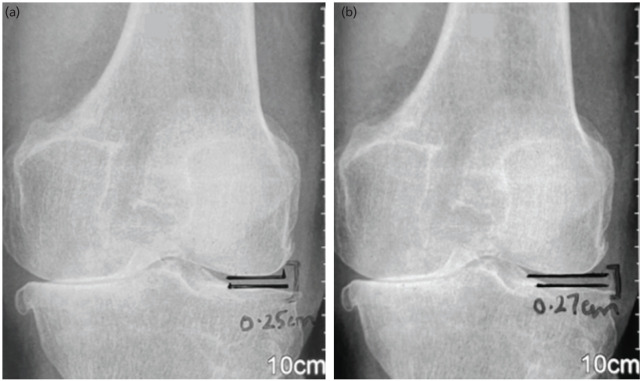

Materials and methods: A comparative study was conducted on 32 patients with medial compartment osteoarthritis of knees. While the neutral group of 16 patients was constituted of those with an anatomical-lateral-femoro-tibial-angle (aFTA) 176-180º, varus group comprised an equal number of patients with an aFTA >180º. A home-based 12-week strength-training program involving weekly visits to hospital for supervised sessions was administered. The outcome measures were visual-analog-scale (VAS), medial patello-femoral joint tenderness (MPFJT), time-up-and-go-test (TUGT), stair-climb test, step test, WOMAC, IKDC scores, aFTA, hip-knee-ankle (HKA) angle, lateral-tibio-femoral-joint-separation (LTFJS), and horizontal-distance-from-centre-of-knee-to-Mikulicz-line.

Results: There was a significant increase in quadriceps strength (p<0.01) in both groups. Values for neutral group with VAS score (p=0.01), MPFJT (p=0.01), TUGT (p=0.01), timing of the stair climb test (p=0.01), WOMAC (p<0.01), and IKDC (p=0.03) were better compared to varus group with VAS score (p=0.13), MPFJT (p=0.03), TUGT (p=0.90), timing of stair climb test (p=0.68), WOMAC (p<0.02), and IKDC (p=0.05). Varus group also showed an increase in aFTA and LTFJS in 12 patients, increase in HKA in 11, and increase in horizontal distance from the centre of knee to the Mikulicz line in 7 patients.